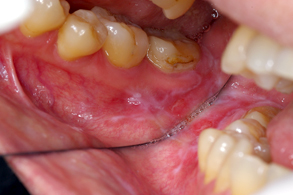

口腔扁平苔癬歯科口腔外科症例解説東京銀座シンタニ歯科口腔外科クリニック。